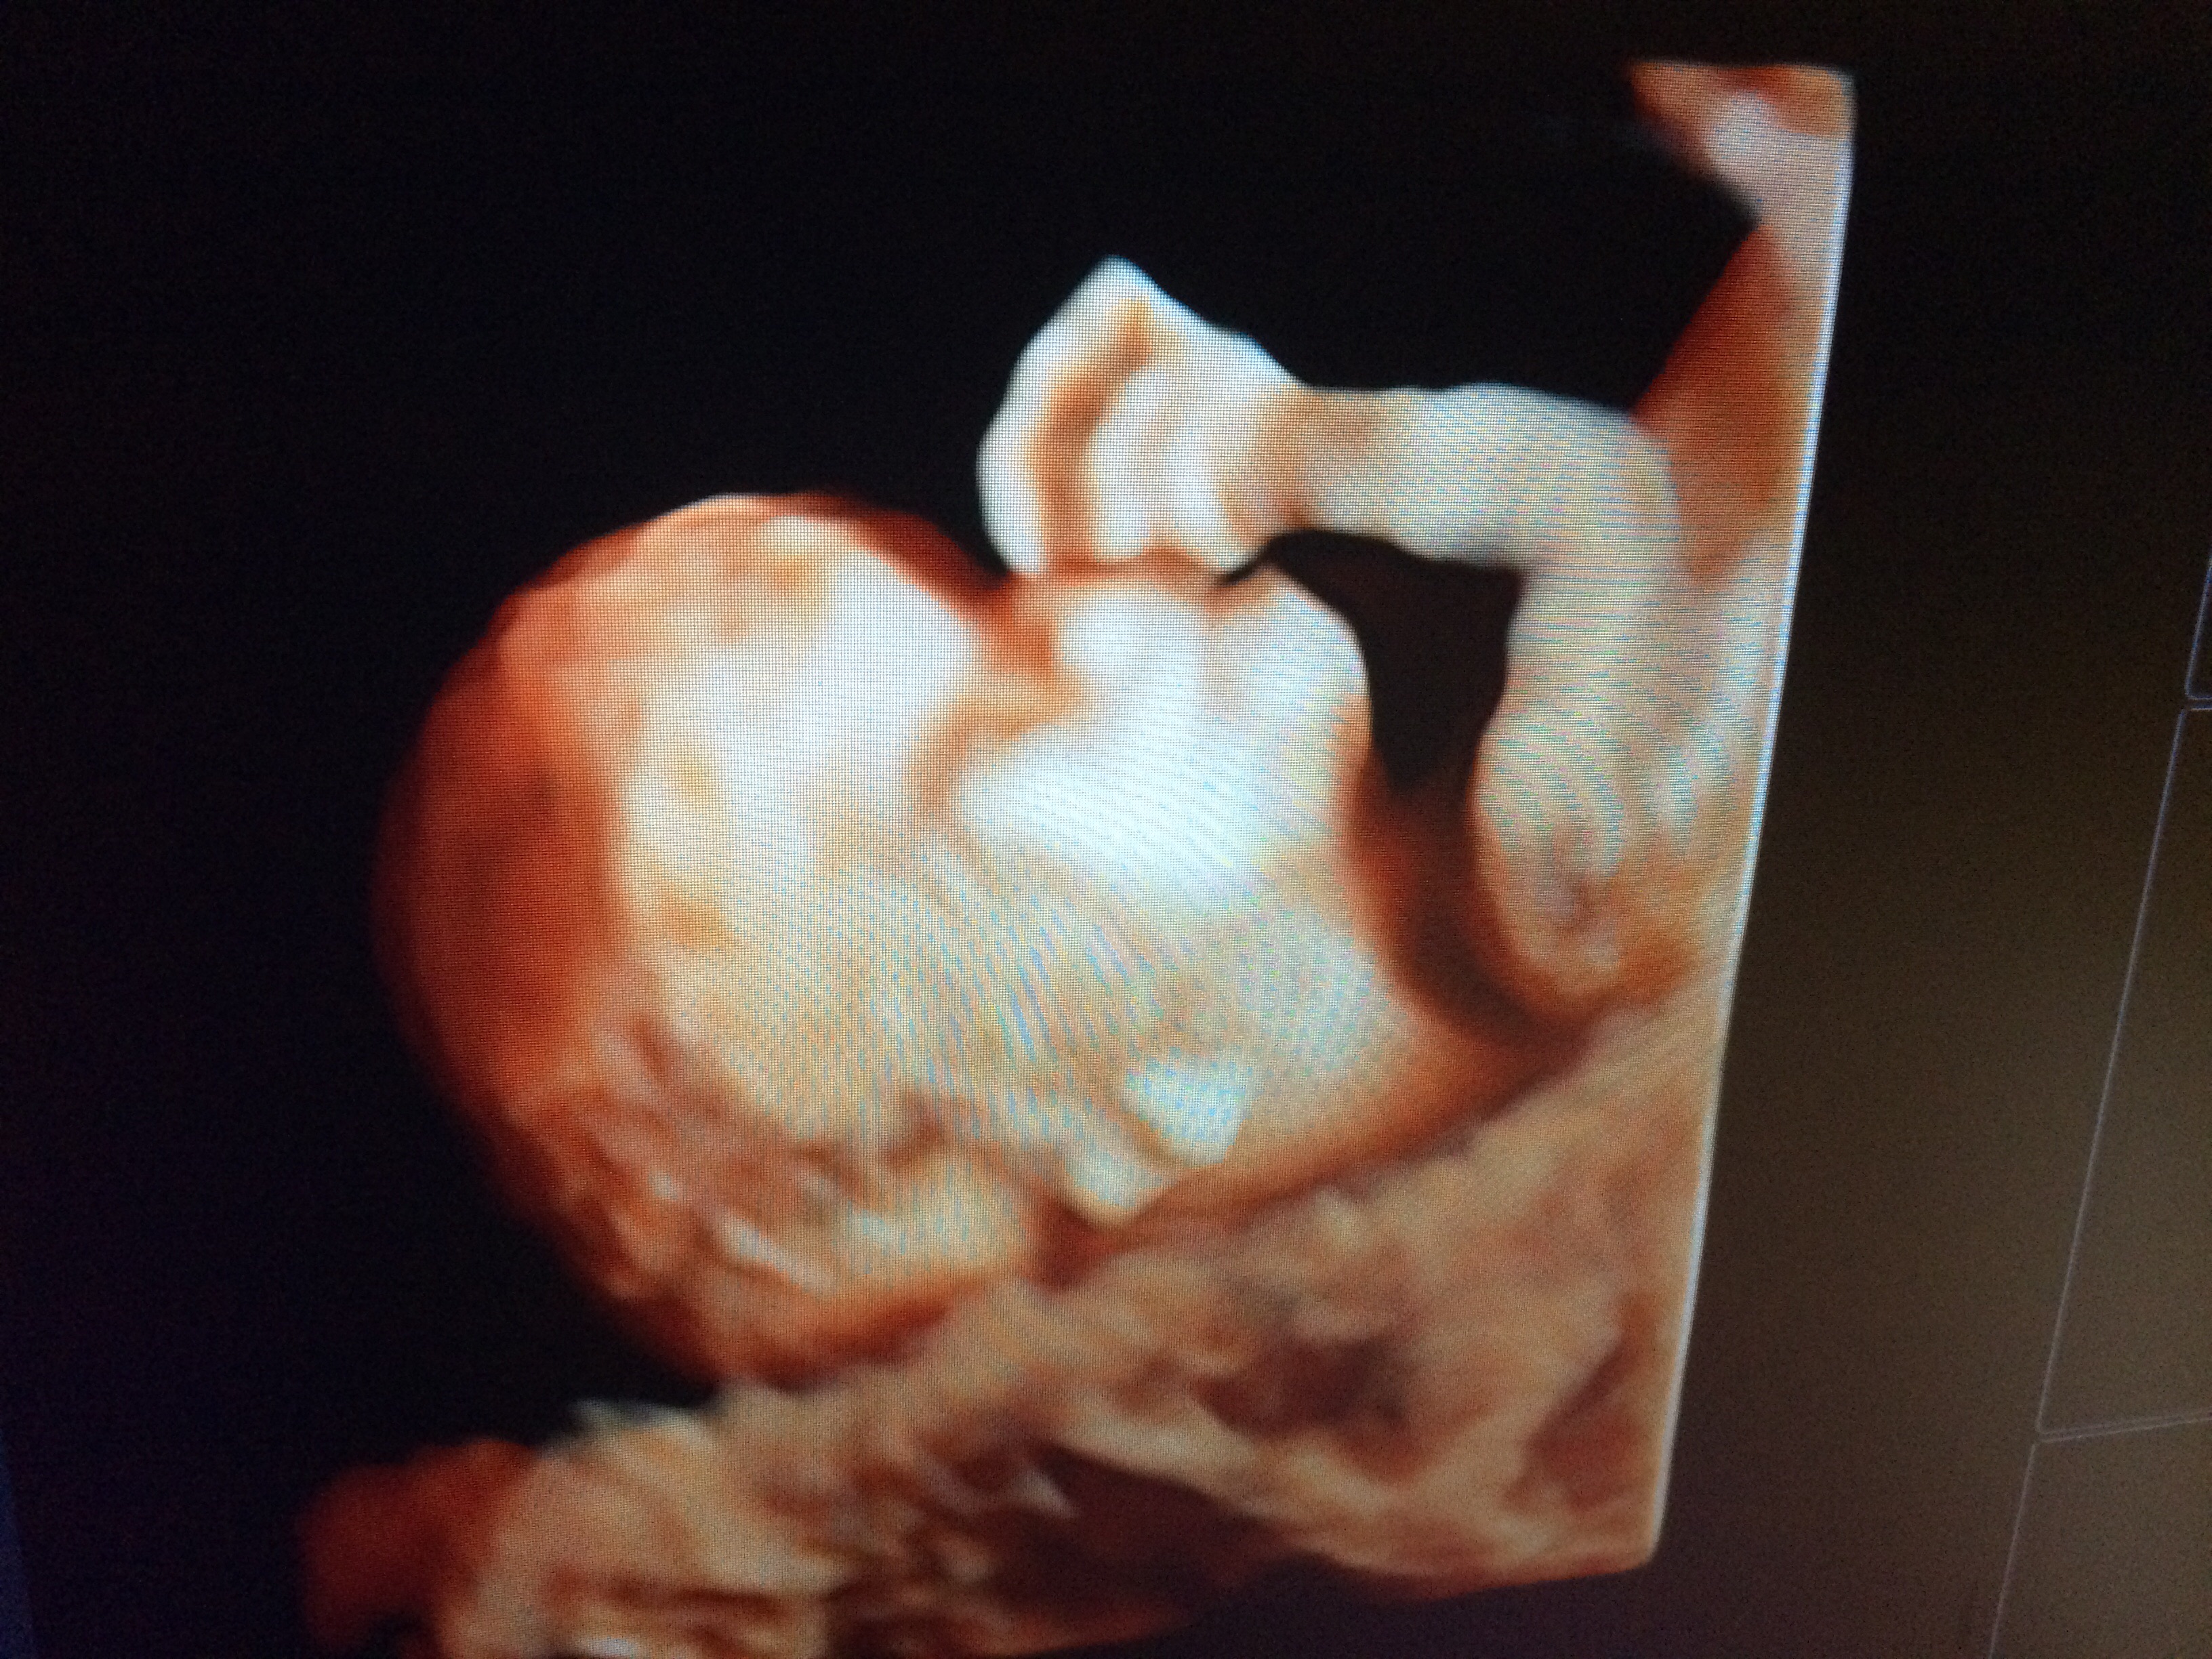

NT U/S went as good as it could have! My results were the best they could possibly be and HB was 145. Measured at 12weeks 6days but my due date won't change so still 5/13/15. Got some good pics of baby and it was moving its little arms all around. So cute! Tech said I have a posterior placenta so that means I'll be able to feel the baby move earlier. Next prenatal appt is 11/26 then after that one we will have the anatomy scan and be able to know the sex!